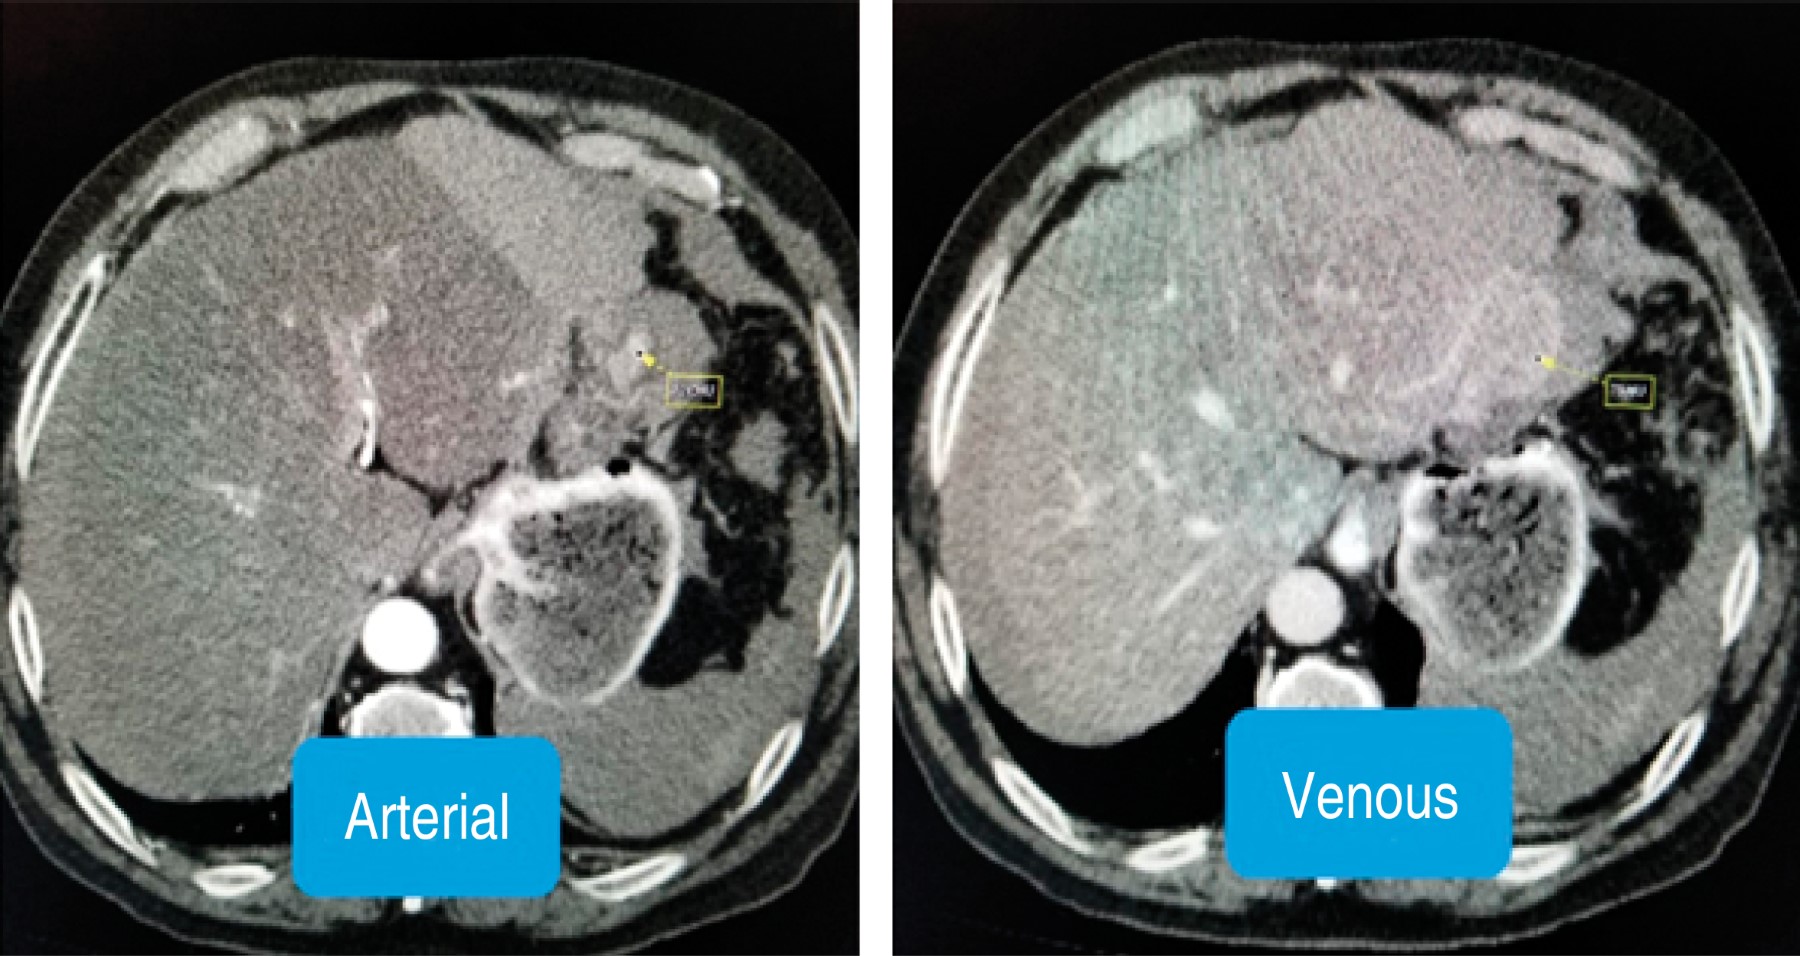

On physical examination, the patient was conscious and oriented; on admission, vital signs were heart rate of 92 per minute, blood pressure of 102/80 mmHg, oxygen saturation of 94% with FiO2 of 36%. The abdomen was distended with decreased hydroaerial sounds, and on palpation, there was evidence of involuntary muscle resistance with positive Dunphy's sign. Laboratory and imaging tests were performed with the following results: leukocytes: 14.7 K/µl, neutrophils: 77.7%, hemoglobin: 11.1 g/dl, hematocrit: 33.8%, platelets: 236,000 K/µl; arterial blood gases on admission showed a pH of 7.11, pCO2 of 36 mmHg, PO2 60 mmHg, HCO3 11.40 mEq/l, base excess -17.20 mEq/l, and lactate 9.70 mmol/l. It was decided to administrate crystalloid solutions and to perform a CT scan of the abdomen without contrast that showed a liver with a heterogeneous tomographic density of micronodular appearance, with a decrease in size of the right lobe, findings probably related to liver cirrhosis. In addition, perihepatic fluid in the perisplenic, and parietocolic gutters, and in the pelvic cavity was approximately 1,500 cm3 (Figure 1). Subsequently, the patient again refers a sensation of weakness with the following vital signs: heart rate of 115 per minute, and blood pressure of 80/50 mmHg, so it was decided to transfer him to the operating room urgently. A laparoscopic surgery was started, but due to the findings, it was decided to convert to laparotomy during the trans-surgical procedure, where 2,000 ml of hemoperitoneum were identified. The hemoperitoneum was drained and hepatic segmentectomy of segment II was performed (Figure 2); two red blood cell packages were transfused during the trans-surgical procedure. The patient was transferred to the general ward with hemodynamic stability; however, in the control examinations hemoglobin was found to be 8.5 g/dl, so it was decided to transfuse two more packs of red blood cells and two packs of fresh frozen plasma, after which his evolution was without complications. The Jackson Pratt drainage was removed and on the fourth day of hospitalization, he was discharged with oral paracetamol 1 gram every eight hours for five days.

Hepatocellular carcinoma (HCC) is the most common primary malignant neoplasm of the liver worldwide; it represents 90% of liver neoplasms,5 with approximately 500,000 cases diagnosed per year. Spontaneous rupture occurs in 20% of the cases producing hemoperitoneum, with which the mortality rate increases up to 25%.6 The imaging test of choice for diagnosis, treatment, and define the extension of liver tumors is the three-phase tomography, which has a diagnostic accuracy of 68 to 90%.5

Figure 1